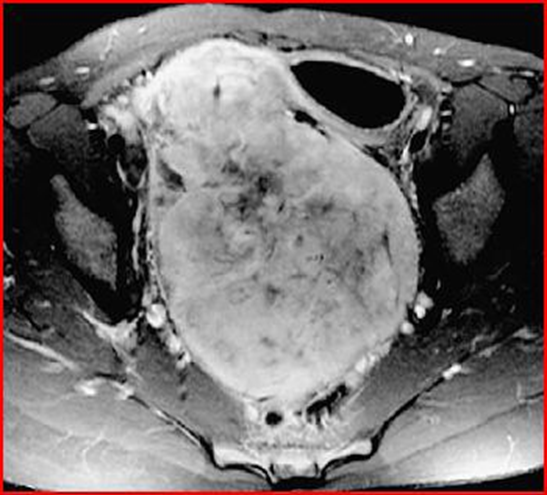

It is also interesting to observe the MRI images obtained by Weingertner et al [37] which differ slightly from the usual images previously described by Ferrozzi and Mitsumori, regarding the ovarian localization of non-Hodgkin’s lymphoma (Figures 19-21).

In fact, Weingertner describes a case of ovarian lymphoma that mimics a metastatic ovarian tumor. In fact, the patient, in addition to presenting an elevation of tumor markers such as CA125 which are generally used as a warning light for ovarian cancer, did not present any typical symptoms of lymphoma, such as fever or night sweats. It has a pelvic mass measuring 8 x 11 x 15 cm.

Figure 19: Transverse MRI image showing a solid and heterogeneous pelvic mass, with a necrotic center. The volume of the mass is 8 x 11 x 15 cm.

Figure 21: Sagittal MRI image, showing compression of the bladder, uterus and urinary tract.